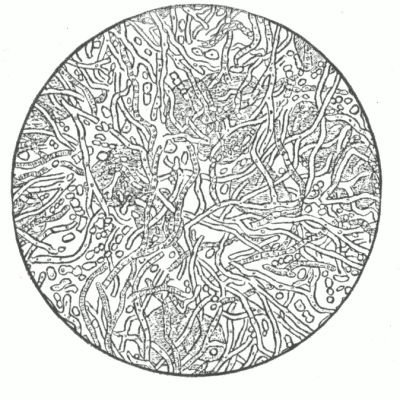

Fig. 1.

Vertical section of the skin—Diagrammatic. (After Heitsmann.)

Fig. 2.

c, corneous (horny) layer; g, granular layer; m, mucous layer (rete Malpighii).

The stratum lucidum is the layer just above the granular layer.

Nerve terminations—n, afferent nerve; b, terminal nerve bulbs; l, cell of Langerhans.

(After Ranvier.)